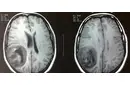

Beyinde kitle ameliyatı, genellikle tümörler, kist veya diğer anormal oluşumların cerrahi olarak çıkarılması amacıyla yapılan bir işlemdir. Bu tür bir ameliyat, beyin dokusuna doğrudan müdahale gerektiği için belirli riskler taşır ve sonrasında hastalar için çeşitli zorluklar ortaya çıkabilir. İşte bu makalede, beyin kitle ameliyatının riskleri ve sonrası hakkında detaylı bir inceleme yapılacaktır. 1. Beyin Kitle Ameliyatının Riskleri Beyin kitle ameliyatı, birçok risk barındırır. Bu riskler arasında şunlar bulunmaktadır:

4. Potansiyel Komplikasyonlar Ameliyat sonrası komplikasyonlar, hastanın genel sağlığını etkileyebilir. Bunlar arasında: